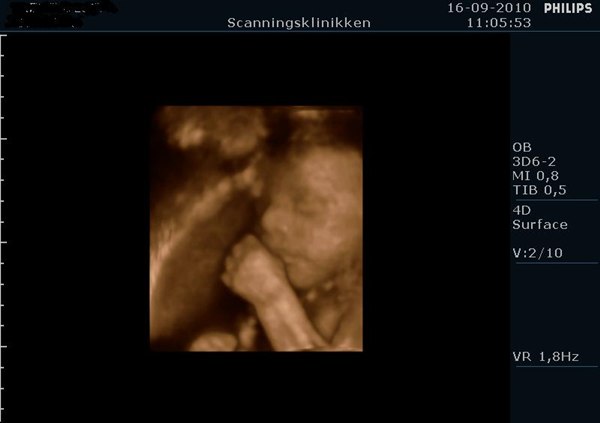

Det så bare så skægt ud med den hikke, og tror nok det kom med på dvden i starten hvor hun lavede 2D...

Ej hvor sjovt, smiler.. Det er da ret specielt at have på dvd

Hehe.. ja, efter sådan en 3D/4D har man bare lyst til at føde og få den lille ud i sine arme